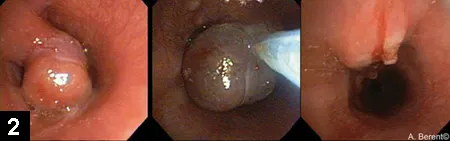

Figure 3. Lateral radiograph of a feline patient after a colorectal stent was placed for colonic stricture

In the author’s experience, colonic stents have been placed in veterinary patients primarily for tumors or strictures (after resection and anastomosis or postradiation therapy). In all cases, colonoscopy is performed to visualize and obtain a biopsy followed by fluoroscopy to guide stent placement over a guide wire (Figure 3); patency can be reestablished immediately. The stent has been seen to be incorporated into the colonic mucosa within 4 days.